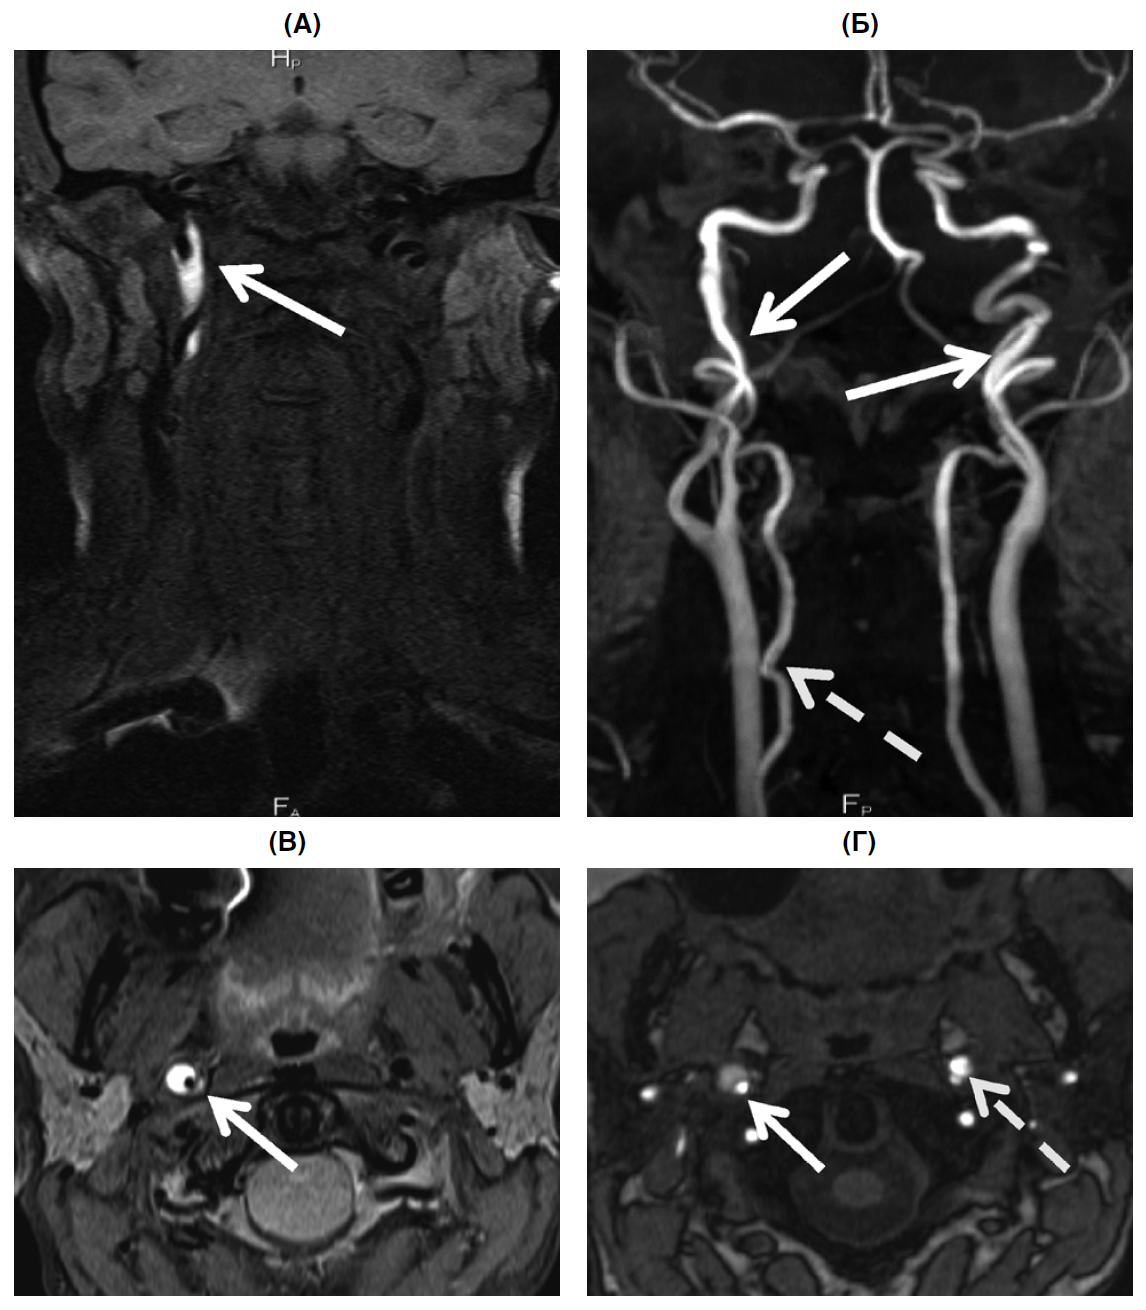

В неврологическом статусе: синдром Горнера справа, гиперестезия кожи волосистой части головы справа, в остальном — без особенностей. При МРТ артерий шеи с использованием 3D-TOF МРА (магнитно-резонансная ангиография) и T1ВИ Fat Sat (Т1-взвешенные изображения с подавлением сигнала жира): в стенке проксимального отдела правой ВСА на расстоянии 1,7 см от устья, на протяжении около 5 см определялась зона повышенной интенсивности МР-сигнала на Т1ВИ Fat-Sat — интрамуральная гематома в форме полулуния в аксиальной проекции (наружный диаметр артерии около 7–9 мм, внутренний просвет — 2–3 мм). Правая ВСА извита, в левой выявлены извитость, неравномерность ее диаметра перед входом в полость черепа, формирование двойного просвета протяженностью около 2 см на этом же уровне. Дополнительно обнаружена непрямолинейность хода правой позвоночной артерии в сегменте V2 (рис. 1). Таким образом, согласно данным МРА, у больной имелись признаки сосудистой дисплазии — извитость магистральных артерий шеи и локальный двойной просвет в стенке левой ВСА, причиной которого, скорее всего, являлась ранее развившаяся и асимптомно протекавшая диссекция левой ВСА.

Рис. 1. МРТ артерий шеи, Т1ВИ Fat-Sat без контрастного усиления и 3D-TOF МРА больной Л., 45 лет, с диссекцией правой ВСА

Примечание. А, В: Т1ВИ Fat-Sat, коронарная (А) и аксиальная (В) проекции. В стенке правой ВСА зона повышенной интенсивности МР-сигнала полулунной формы на аксиальных изображениях (стрелки), протяженностью около 5 см — интрамуральная гематома. Б — 3D-TOF МРА, 3D-реконструкция, неравномерное сужение экстракраниального отдела правой ВСА. Формирование двойного просвета в левой ВСА протяженностью около 2 см, извитость левой ВСА перед входом в полость черепа (стрелка), непрямолинейность хода правой позвоночной артерии в сегменте V2 (пунктирная стрелка). Г — 3D-TOF МРА, «исходные» данные, в стенке правой ВСА интрамуральная гематома полулунной формы (стрелка), наружный диаметр артерии увеличен, просвет артерии сужен, формирование двойного просвета в левой ВСА (пунктирная стрелка).